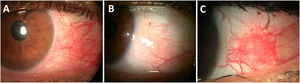

Clinical manifestations and diagnosisPUK patients typically present with an acute onset of tearing, injection, photophobia, foreign body sensation, and pain of variable intensity with or without vision loss. Slit-lamp examination reveals a crescent-shaped peripheral ulcer with stromal thinning and infiltration (Fig. 5).131 A varying degree of inflammation involving the adjacent conjunctiva and sclera can also be seen.137 The most extensive series of RA-associated PUK eyes reported concomitant anterior diffuse, nodular, and necrotizing scleritis in 46%, 21%, and 15% of eyes at PUK onset, respectively.12

Corneal ulceration associated with Rheumatoid Arthritis (RA). (A) Peripheral ulcerative keratitis in an RA patient with associated Sjögren syndrome, showing a dense inferior peripheral circumferential stromal infiltrate. (B) Positive fluorescein staining of the same eye showing an extensive epithelial defect. (C) Central corneal ulceration (positive fluorescein staining) in an aged woman with a long history of uncontrolled RA.